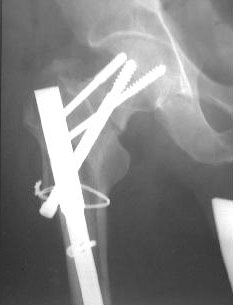

The implant selection was right but application technique and length of the nail were not. Lateral x-rays of the hip should be taken to confirm reduction of the femoral neck (bilaterally?).

In my opinion both fractures sould be revised with closed interlocking nailing with the same nail, appropriate length using two proximal locking screws to the head. Two screws for distal locking must be also used because these are very unstable fractures.

I would probably start out with a fluoroscopic evaluation of the stability of thefixation. If it was grossly unstable, I would think that at least the neckfracture needs better reduction and fixation - but there appears to be nothingleft on the lateral side to hold a side-plate or screws needed for neck fixationwithout a proper interfragmentary reconstruction of the proximal femur and thenthat would mean - even with indirect reduction - a big exposure and a big plate.

We fluoroscoped every thing in the OR under anesthesia. It was clear that the Ltproximal side is unstable, in mal-position and the nail is probably outproximally.

On the Rt side, the proximal construct was stable but the distal (the shaft fx)was not.